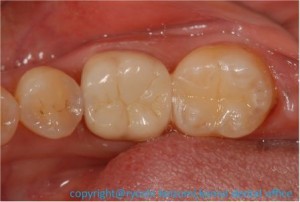

図8 完成

ついに完成しました!

冠と詰め物を精密に作ってくださる優秀な歯科技工士さんと、

アシスタントの歯科助手さんとのコラボのたまものです。

そして何より、患者さんが一番頑張って治療を受けてくださったと思います!

治療前の違和感は無事解決し、納得のいく仕事ができました。

以前よりも噛みやすくなり、見た目もきれいになって嬉しい!、と

喜んでおられました!

この瞬間、この言葉、そして患者さんの嬉しそうな顔が、

歯科医師人生で一番嬉しく感じる時間の1つです。